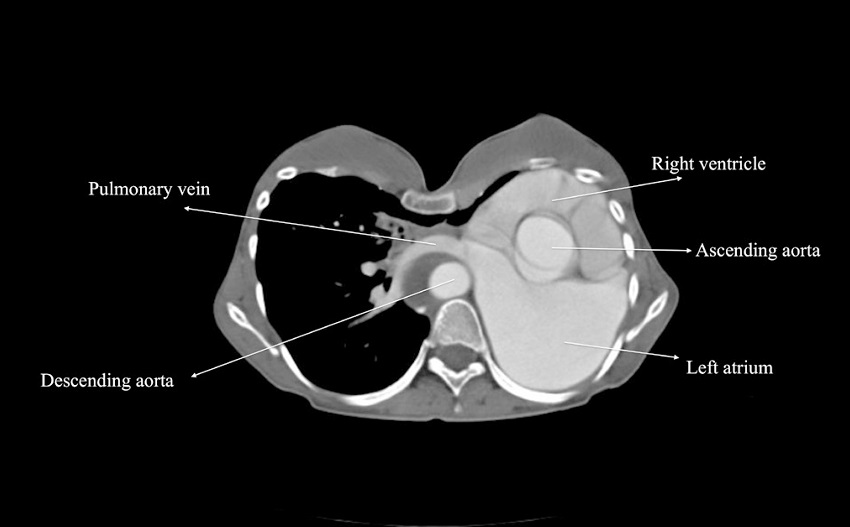

Transthoracic echocardiogram revealed severe mitral regurgitation due to myxomatous mitral valve with bileaflet prolapse and chordal elongation, secondary pulmonary hypertension, and tricuspid regurgitation with a dilated right atrium. Her ejection fraction was 35%, left ventricle end-diastolic diameter was 72 mm, and end-systolic diameter was 59 mm. She also had a borderline ascending aortic aneurysm measuring 40 mm in diameter. Pulmonary function test demonstrated reduced forced vital capacity (FVC), 1.11 L (31.7% of predicted), and reduced forced expiratory volume in 1st second (FEV1), 1.05 L (34.6% of predicted). A contrast-enhanced computed tomography (CT) scan was performed to examine the mediastinal structures and alternative cannulation sites (Figure 2). Heart and great vessels were displaced to the left, and the right lung was enlarged and crossing the midline, anterior to the heart. The proxymal ascending aorta was 40 mm in diameter. Additionally, a chronic type B aortic dissection was present. CT scan revealed that the ascending aorta and the superior and inferior venae cavae were suitable for cannulation.